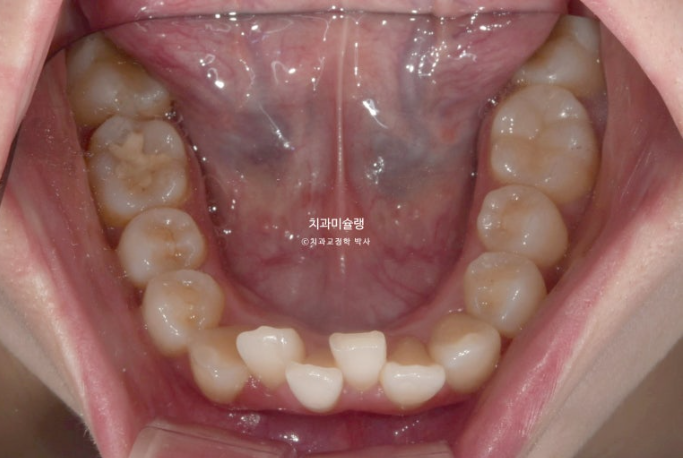

앞니도 많이 삐뚤합니다.

예쁜 배열위에 고정식 철사 유지장치까지 붙은 모습입니다.

어긋나 있던 중심선은 정확히 맞으며 깊게 물리는 과개교합이 해소되어 이제 아래 앞니가 정상적으로 보입니다.

뿐만 아니라 치아 높낮이 불규칙으로 인해 들쑥날쑥 했던 아래 앞니가 배열되면서 잇몸라인도 어느정도 정리가 되었습니다.